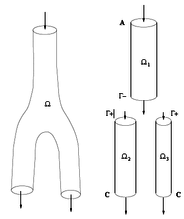

Boundary conditions from multiscale modeling of circulation: Another approach to impose the boundary conditions is to use reduced models, as 1D model or 0D (lumped) models. 1D and 0D models are mathematical models able to reproduce the systemic and pulmonary circulation. Figure 10 shows a standard approach to provide realistic local boundary conditions for 3D CFD simulations at the specific arterial domain using 1D models of the entire arterial tree and 0D models at the distal ends[83]. 1D model solves the Navier-Stokes equations under some assumptions (see appendix 9) and lumped models (0D models) can be derived from electrical circuit analogies where blood flow is represented by the current and arterial pressure by the voltage. Usually the electrical components of these circuits are resistances, inductances and capacitors. Where resistances represent arterial and peripheral resistance that occur as a result of viscous dissipation inside the vessels, capacitors represent volume compliance of the vessels that allows them to store large amounts of blood, and inductors represent inertia of the blood[75]. The values of these electrical components can be estimated from physical data of the subject [84][85]. This approach is quite used because it is capable to account for the effect of local pathological conditions on the whole circulatory system, providing realistic boundary conditions for the 3D problem [75][79][86].